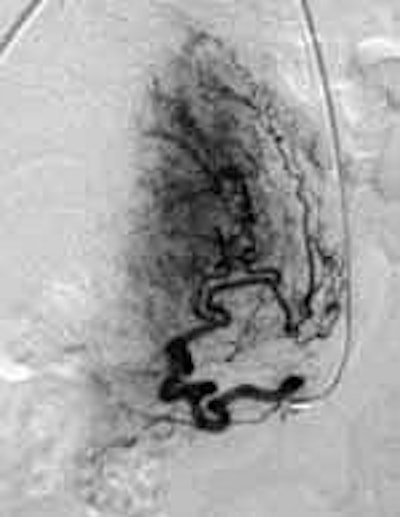

![]() |

| Pre-UFE angiogram with catheter insertion. Contrast highlights fibroids. Image courtesy of Dr. Neal Joseph, Radiology Associates of Hollywood, FL. |